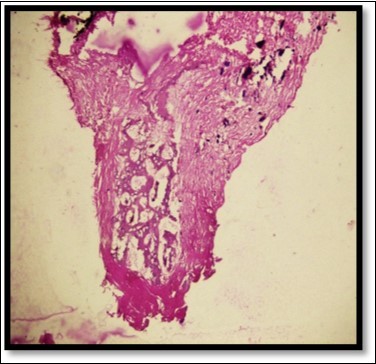

A 13year-old male patient reported to the Department of Pediatric and Preventive Dentistry with a chief complaint of the presence of a ‘lump’ in the lower right back region. The history revealed that the patient had buccal abscess in relation to 85 two months back for three days which reduced on medications. The tooth (85) exfoliated within 1 month and soon after the exfoliation, patient noticed a lump in that region. The lump was painless and increased in size in the last one month. Patient experienced discomfort in speech since the last one week. No abnormality or asymmetry was noted on extra-oral examination. Intraoral clinical examination revealed a painless, fibrous nodular mass with a sessile base in the right lower gingival margin extending from the mesial surface of 44 to distal surface of 45 on the lingual surface, measuring approximately 2 cm in diameter and showing a rough surface and color similar to that of the adjacent mucosa(Figure 1)

Figure 1.Pre operative size and extent of lesion

Pre operative size and extent of lesion